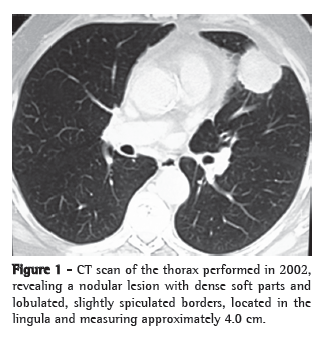

We present the case of a 71-year-old male patient submitted to left upper lobe lobectomy with pericardial resection due to localized invasion and mediastinal lymphadenectomy five years ago (Figure 1). The pathological stage was IIB (T3N0M0). A contralateral pulmonary lesion (0.8 cm) was found in the upper segment of the right lower lobe during a follow-up imaging study (Figure 2). This lesion had not been seen in previous imaging studies. The patient was asymptomatic, had no comorbidities and presented no history of liver disease. He was a former smoker (30